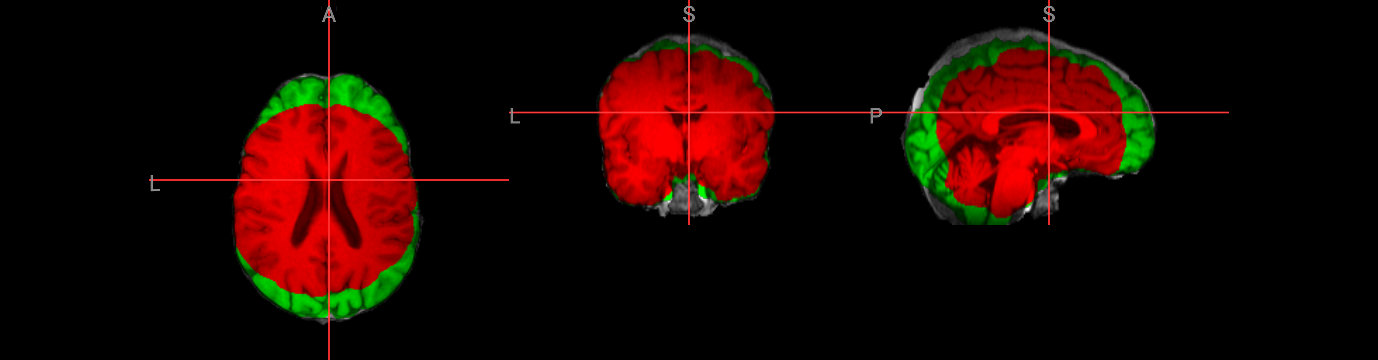

Brain extraction is a fundamental preprocessing step in neuroimaging analysis, particularly critical for structural image segmentation where precision matters most. While BET is straightforward to use, achieving optimal results often requires understanding how to fine-tune parameters for challenging datasets. This interactive version covers the core BET fundamentals, including parameter adjustment techniques for difficult images, and troubleshooting approaches for problematic cases. The hands-on format allows you to experiment with different settings and immediately see their effects on brain extraction quality.